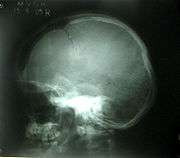

Linear fracture

Linear skull fractures are breaks in the bone that transverse the full thickness of the skull from the outer to inner table. They are usually fairly straight with no bone displacement. The common cause of injury is blunt force trauma where the impact energy transferred over a wide area of the skull.

Linear skull fractures are usually of little clinical significance unless they parallel in close proximity or transverse a suture, or they involve a venous sinus groove or vascular channel. The resulting complications may include suture diastasis, venous sinus thrombosis, and epidural hematoma. In young children, although rare, the possibility exists of developing a growing skull fracture especially if the fracture occurs in the parietal bone.[6]